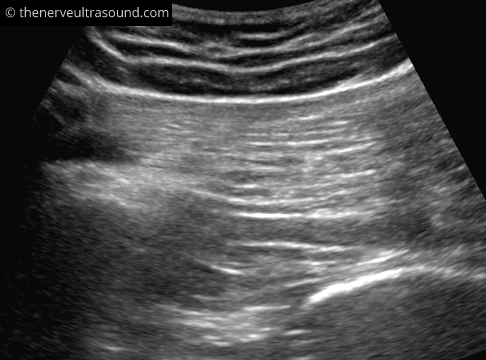

The structures at the gluteal region lie deep, often requiring a lower frequency probe (e.g. 5-8 MHz) to have enough penetration. The piriformis muscle serves as leading structure. Palpation of the border of the sacrum and the greater trochanter helps to identify the expected course of the piriformis muscle. To start off with, it is helpful to place the probe proximal on the ileum with the ultrasound-probe in the orientation of the expected course of the piriformis muscle. Moving distally the cortex of the ilieum bone soon disappears and the piriformis muscle will become visible from its origin on the ventral surface of the sacrum running over the dorsal aspect of the acetabulum to the greater trochanter of the femur.

Passive internal and external rotation of the hip may help to delineate the piriformis muscle.

The sacral plexus with the sciatic nerve lies deep to the piriformis muscle medial to the bone corresponding to the dorsal aspect of the acetabulum. As a variant, the nerve or parts of it can also run through the muscle or dorsal to it.